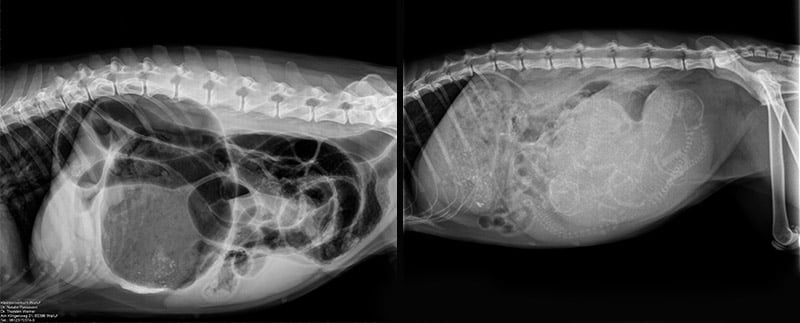

Abdomen (Bauchraum):

Magen (zum Beispiel bei einer Magendrehung), Darm, Leber, Milz, Nieren, Blase lassen sich ebenfalls gut im Röntgen untersuchen.

Um eine noch bessere Aussage bei bestimmten Fragestellungen zu bekommen, kann es notwendig sein, ein Kontrastmittel einzusetzen. Dieses ist röntgendicht und kann dadurch bestimmte Strukturen besser darstellen oder sogar die Funktion eines Organs überprüfen

Es gibt ein spezielles Kontrastmittel für den Magen-Darm- Trakt. Hiermit kann die Durchgängigkeit der Magen- Darm- Passage überprüft werden und es können auch Engstellen oder Aussackungen in der Speiseröhre festgestellt werden.

Ein weiteres spezielles Kontrastmittel gibt es für die Harnwege. Hiermit können zum einen Engstellen oder Rupturen im Bereich der Harnleiter, der Blase oder Harnröhre beurteilt werden. Zum anderen kann – in einem gewissen Rahmen - auch die Funktionstüchtigkeit der Nieren überprüft werden.